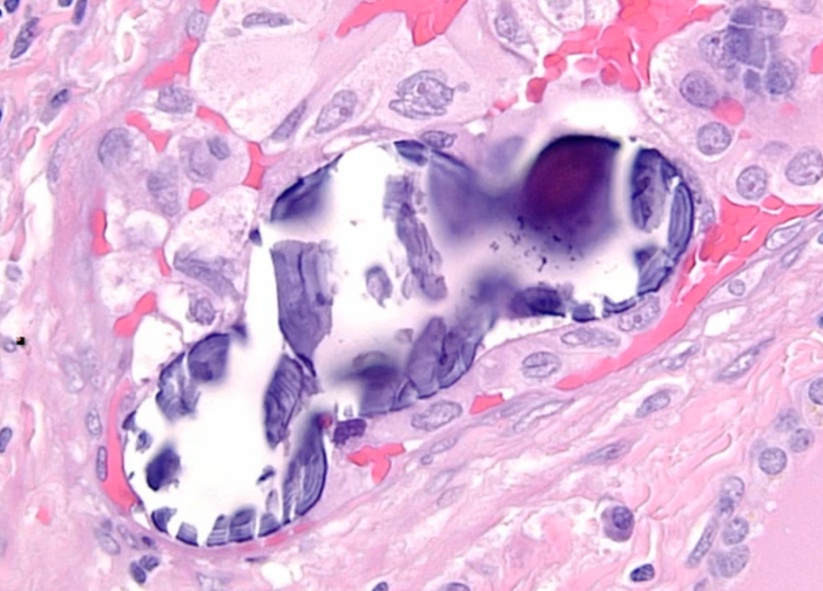

_Histology:

Orphan Annie eye nuclei: no nuclei

Nuclear grooves: line through nucleus

Psamomma bodies

.,